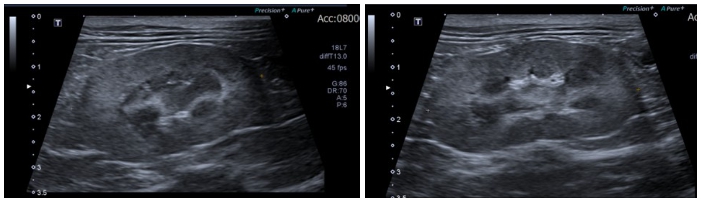

입원 18일 차에는 상태가 안정되어 통원 치료가 가능할 정도로 호전되었습니다. ▼

사진: 투석 치료 7개월차에 촬영한 검사 결과로, 신장 수치가 정상 범위 내에서 잘 유지되고 있습니다. ▼